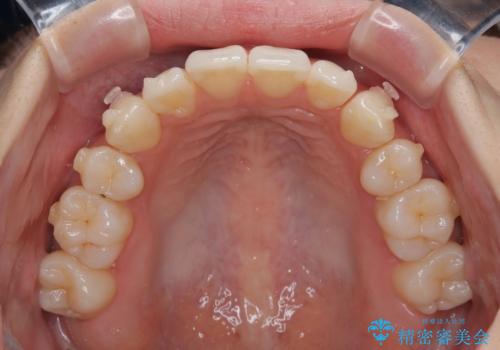

1. 抜歯矯正の軽度後戻りを解消 インビザライン矯正の治療前